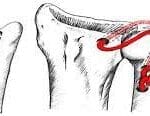

Surgical Treatment – If Needed

Surgery may be advised if symptoms persist despite 3 months of conservative care.

- Distal Clavicle Excision (Mumford Procedure):

- Performed via keyhole surgery (arthroscopy)

- Small portion (no more than 8 mm) of the collarbone is removed

- Recovery is quick, with return to light activity in 3 weeks and full lifting after 12 weeks